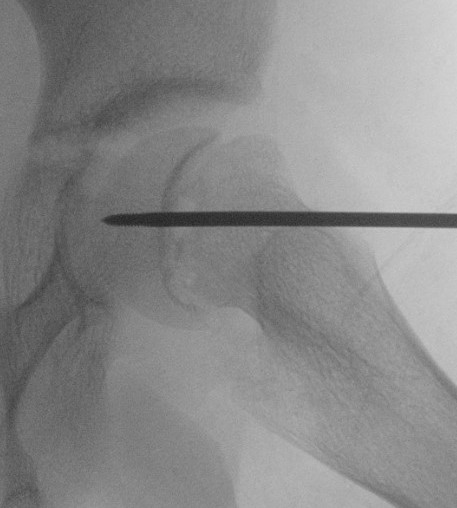

Intra-capsular / Subcapital

Types

Dunn

- trapezoid osteotomy

Fish

- cuneiform